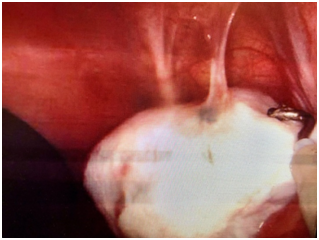

The patient underwent robotic single-incision laparoscopic surgery (SILS) resection of endometriosis, ovarian cystectomy, lysis of adhesions, and cystoscopy by Minimally Invasive Gynecologic Surgery (MIGS) team. After completion of the patient’s pelvic surgery, the thoracic surgery team performed bilateral video-assisted laparoscopy surgery (VATS) with assistance from the MIGS to help identify suspicious lesions. Intraoperative evaluation revealed thoracic endometriosis confined to the pleura of the lungs and the diaphragm. These lesions were resected via electrocautery (Figures 1–3). No parenchymal lung lesions were identified. The patient had an uncomplicated recovery and postoperative phase. Upon discharge the patient was started on oral contraceptive pills (OCPs). Based on the clinical presentation and intraoperative findings the patient was diagnosed with thoracic endometriosis.

Figure 3 Lesions on the central tendon of the diaphragm (Diaphragmatic Endometriosis).